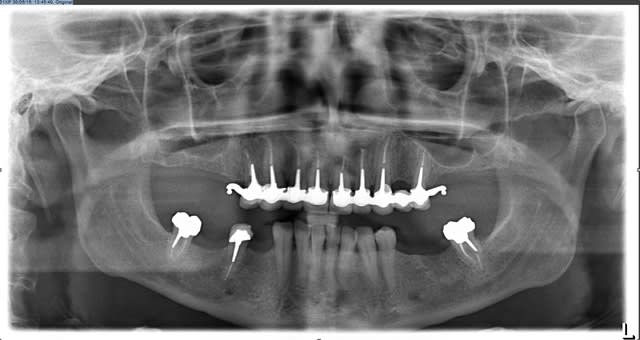

Salut cingulum, je n'aime faire des bridges en mélangeant des piliers vivants et non vivants, et au vu de l'état des dents j'ai préféré réaliser les endo (22 p 4, 12 et 13 nécrosées avec caries cervicales++++...). En ce qui concerne les inlay core, je ne réalise pas beaucoup de rmipp, de plus je me vois mal paralléliser autant de piliers.

Les armatures des bridges céramo-métalliques ont été usinées donc je pense qu'on minimise pas mal les risques de fracture. En revanche les stellites ont été réalisés de manière conventionnelle.

pour info voici brièvement les étapes

-endo et empreinte des couronnes en bas

-pose des couronnes

-élaboration stellite bas pour créer une belle courbe de spee en bas (stellite du bas terminé)

demande wax up en haut

-grosse séance endo en haut et bridge provisoire

réglage occlusion et enregistrement guidage anterieur

-emp ic

-pose ic + provisoire

-emp bridge

-essayage armature bridge

-essayage bridge haut (demande pei + base d'occlusion)

-essayage bridge + stellite

-finition livraison du tout le même jour.

-doléance